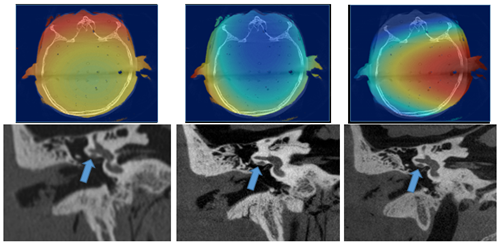

We have a variety of GE Healthcare CT scanners available for basic science and clinical translational research. Ranging from 32 to 256 slices, the scanners are state-of-the-art and feature the latest iterative dose-reducing reconstruction technologies as well as dual-energy imaging capabilities. Time is available for research on a dedicated research CT scanner located in the Wisconsin Institutes for Medical Research (WIMR) facility. The research scanner is a Revolution HD Discovery 750 system. This scanner is located adjacent to two MR systems (both 3T) and near an interventional bi-plane cone beam CT system and an operating suite, facilitating multi-modality research studies. Our facility has access to a micro CT unit and a cone beam CT unit for those interested in comparing these modalities for a specific imaging task.